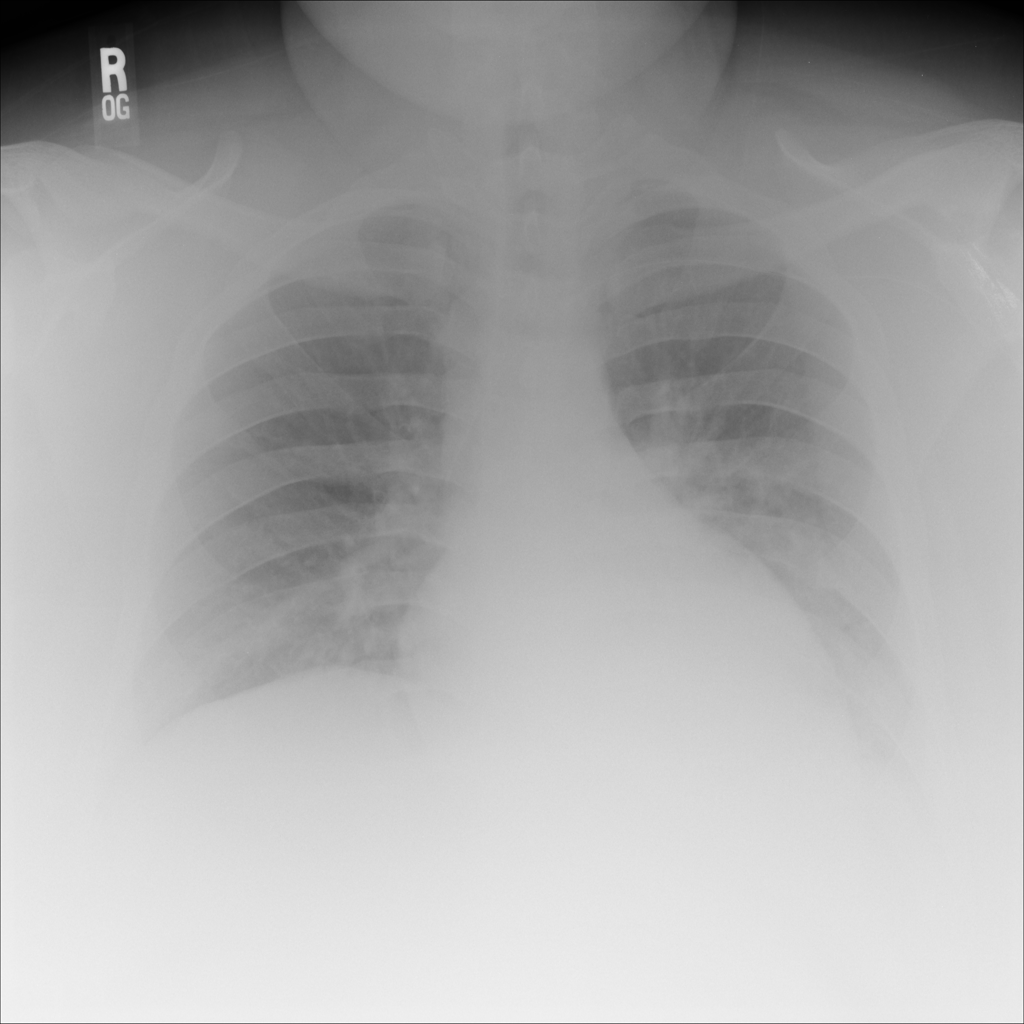

PAT-B733 · IMG-000Consolidation

PAT-B733 · IMG-000

PA